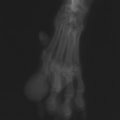

レントゲン検査

レントゲン検査所見から、骨もしくはその周囲組織に発生した腫瘍の可能性が考えられたため、病変部の細胞診検査およびジャムシディ生検針を用いた病変の骨生検を実施した。病理組織検査の結果、非上皮性の悪性腫瘍である“肉腫”と診断された。